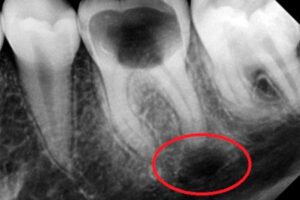

Самый надежный метод диагностики кисты зуба – рентгеновский снимок. На рентгенограмме киста выглядит как темное пятно круглой или овальной формы с четкими краями, обычно у верхушки корня зуба. Однако в некоторых случаях, например, если не весь корень зуба попал в поле зрения снимка, киста может быть не видна или видна частично. Самую полную картину может дать только 3D-томография, которая и позволит со стопроцентной вероятностью подтвердить или исключить наличие кисты.